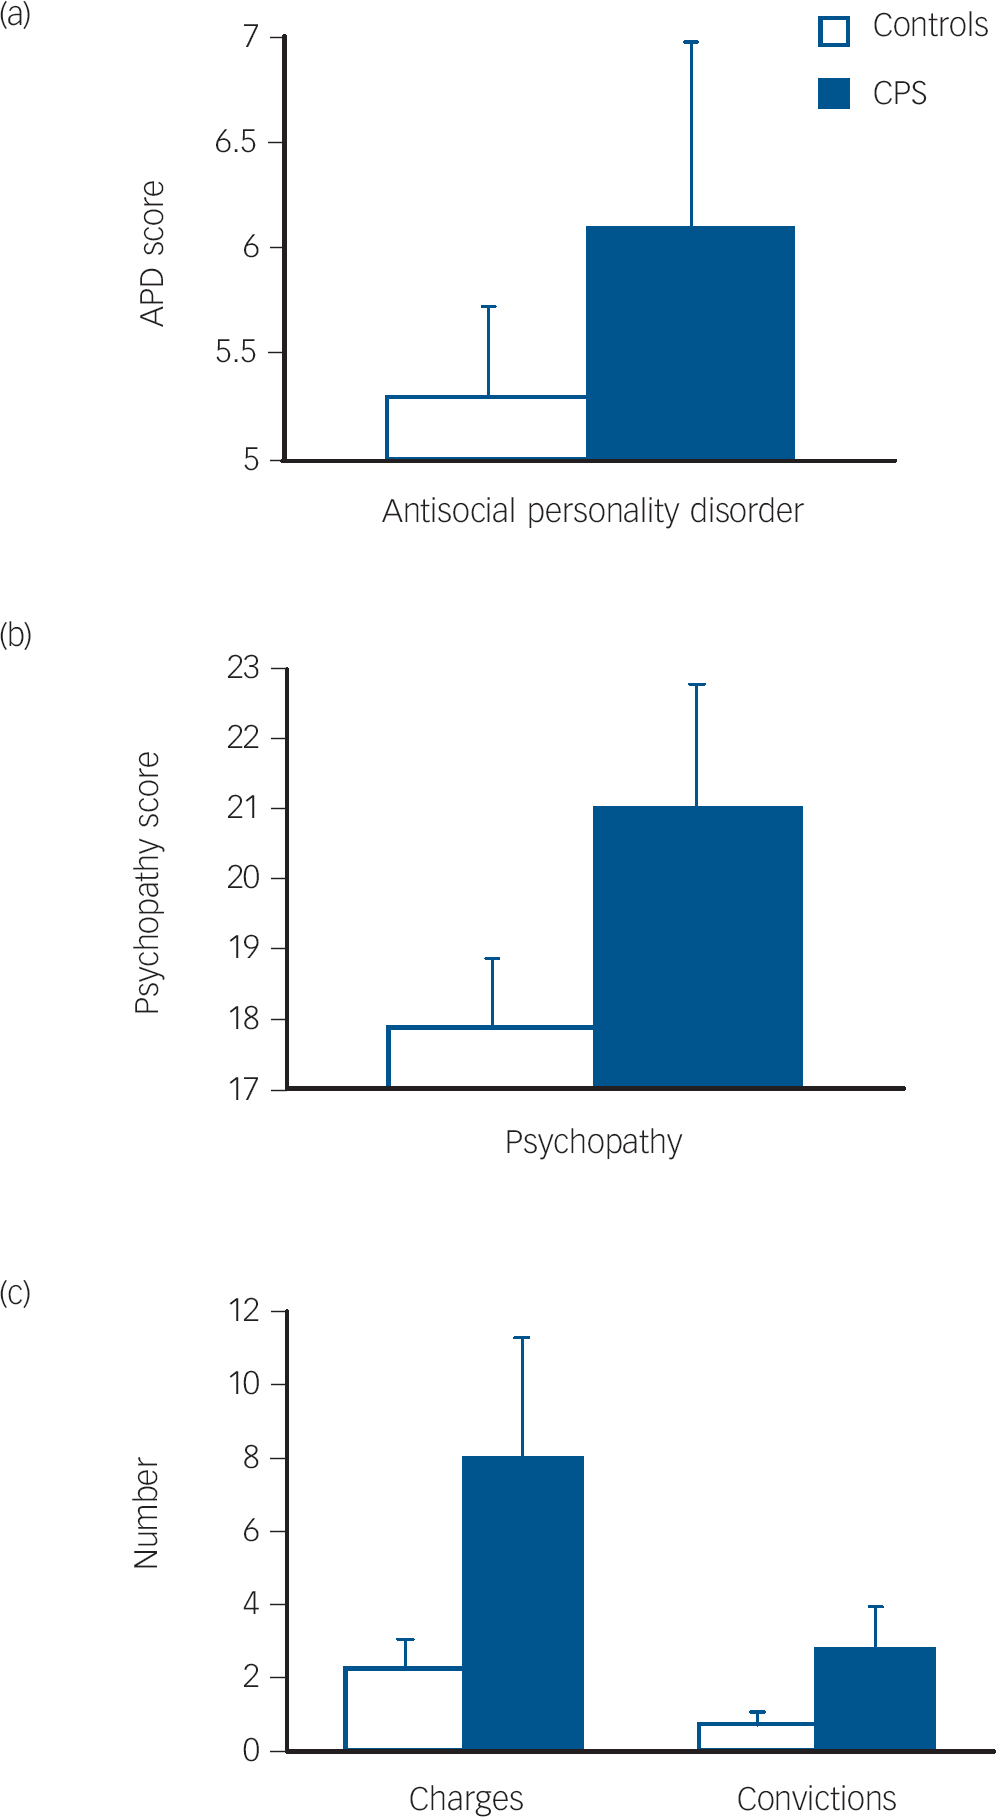

A main effect of CSP grouping indicated higher scores on antisocial personality disorder (mean 6.20) in the CSP group compared with controls (mean 5.29) (F(1,83) = 5.00, P = 0.028, η = 0.057, Fig. 2). Males had higher antisocial personality disorder scores (mean 5.29) than females (mean 0.50) (F(1,83) = 8.85, P = 0.004, η = 0.096), but there was no cavum× gender interaction (P = 0.11).

Fig. 2 Mean scores (with standard error bars) for those with a cavum septum pellucidum (CPS) and those without CSP (controls) on measures of antisocial personality disorder (a), psychopathy (b), and criminal charges or convictions (c).

A main effect of CSP grouping indicated higher psychopathy scores in the CSP group, F(1,80) = 8.21, P = 0.005, η = 0.093 (Fig. 2). A significant CSP×gender interaction indicated particularly higher psychopathy scores in females with a CSP, (F(1,80) = 4.41, P = 0.039, η = 0.052.

Criminal charges and convictions

Those with a CSP present had more criminal charges and convictions than controls (Fig. 2). A multivariate analysis of variance indicated a main effect of CSP grouping on criminal charges and convictions, F(2,83) = 3.80, P = 0.027, η = 0.084. with no group×gender interaction (P = 0.14). Univariate analyses indicated significant effects both for charges (F(1,84) = 7.32, P = 0.008, η = 0.080) and convictions (F(1,84) = 6.00, P = 0.016, η = 0.067).